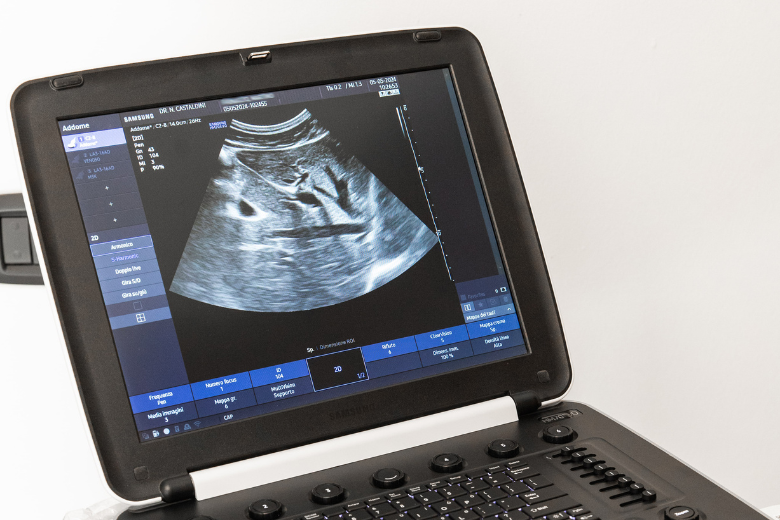

L’ecografia è una tecnica di diagnostica per immagini, di semplice esecuzione, utile ad approfondire lo stato di salute degli organi indagati.

E’ una metodica che utilizza gli ultrasuoni, quindi non è dannosa per la salute, e sfrutta la riflessione di onde sonore (eco) da parte delle superfici che incontrano per ricostruire immagini di tali superfici.

Si effettua per mezzo di una sonda che emette ultrasuoni, onde meccaniche che colpiscono i vari tessuti dalla cute fino agli strati più profondi del corpo; ad ogni interazione con i tessuti, a seconda della densità del tessuto stesso e della sua profondità, una parte di tali onde verrà assorbita ed una parte riflessa. L’analisi e l’elaborazione grafica delle onde riflesse – gli “echi” appunto – restituiscono una immagine delle strutture attraversate dagli ultrasuoni. Le sonde utilizzate possono essere poggiate sulla superficie cutanea, oppure inserite in cavità anatomiche per ridurre la distanza con gli organi da esplorare e migliorare l’accuratezza diagnostica, come per gli esami trans-rettali, trans-vaginali, trans-esofagei o l’eco-endoscopia.